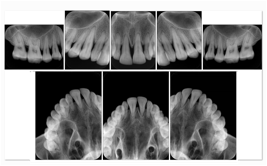

2. A patient requests cosmetic surgery to enhance their facial appearance. The case requires consultation between an orthodontist in New York and an oral surgeon in California. The cephalometric series of 2D projections constructed from a volumetric CT data set that is used for the discussion is arranged by a Structured Display for transfer between the two practitioners.

Cephalometric Series Structured Display

Figure OO-2. Cephalometric Series Structured Display